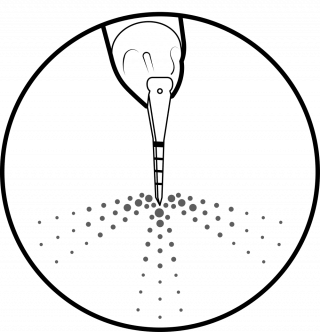

04 AIRFLOW®

Remove biofilm, stains and early calculus:

- Use AIRFLOW® for natural teeth, restorations and implants.

- Remove biofilm supra- and subgingivally up to 4 mm using PLUS 14 μm powder

- Remove remaining stains on enamel using CLASSIC COMFORT Powder.

- Also remove biofilm from gingiva, tongue and palate.

GBT minimizes the use of power and hand instrumentation. AIRFLOW® is minimally invasive on all types of dental tissues: dentine, cementum, enamel and gums. Minimal abrasion for maximum comfort: GBT enables the patient to enjoy natural teeth and implants for much longer.

MAINTAIN ORTHODONTIC APPLIANCES

Orthodontic appliances increase biofilm growth in areas not accessible by daily brushing and traditional prophylaxis. Biofilm creates wire friction, gingivitis and caries. AIRFLOW® with PLUS Powder removes biofilm with full access to critical areas. Safe and effective on teeth and brackets, it prevents caries and hyperplasia.

TREAT EXPOSED DENTINE

Remove exposed biofilm on dentine with AIRFLOW® PLUS Powder and stop the procedure when the color has disappeared. GBT is the only protocol which guarantees minimal invasiveness through direct visual control. AIRFLOW® PLUS Powder with heated water provides maximum comfort and minimal sensitivity.

DETECT CARIES AT AN EARLY STAGE

Caries often develop in areas not accessible by rubber cups or brushes, such as interdental areas, pits and fissures. AIRFLOW® cleans it all. A final check delivers a more accurate, precise and early detection of caries on clean surfaces. Also, it allows fluoride to access a clean tooth more easily.

PRESERVE HEALTHY SOFT TISSUES

GBT step 04 AIRFLOW® removes biofilm in a minimally invasive way. AIRFLOW® PLUS Powder is proven to be gentle on the gingiva and other soft tissues. In contrast, rotary and hand instruments may cause damage.